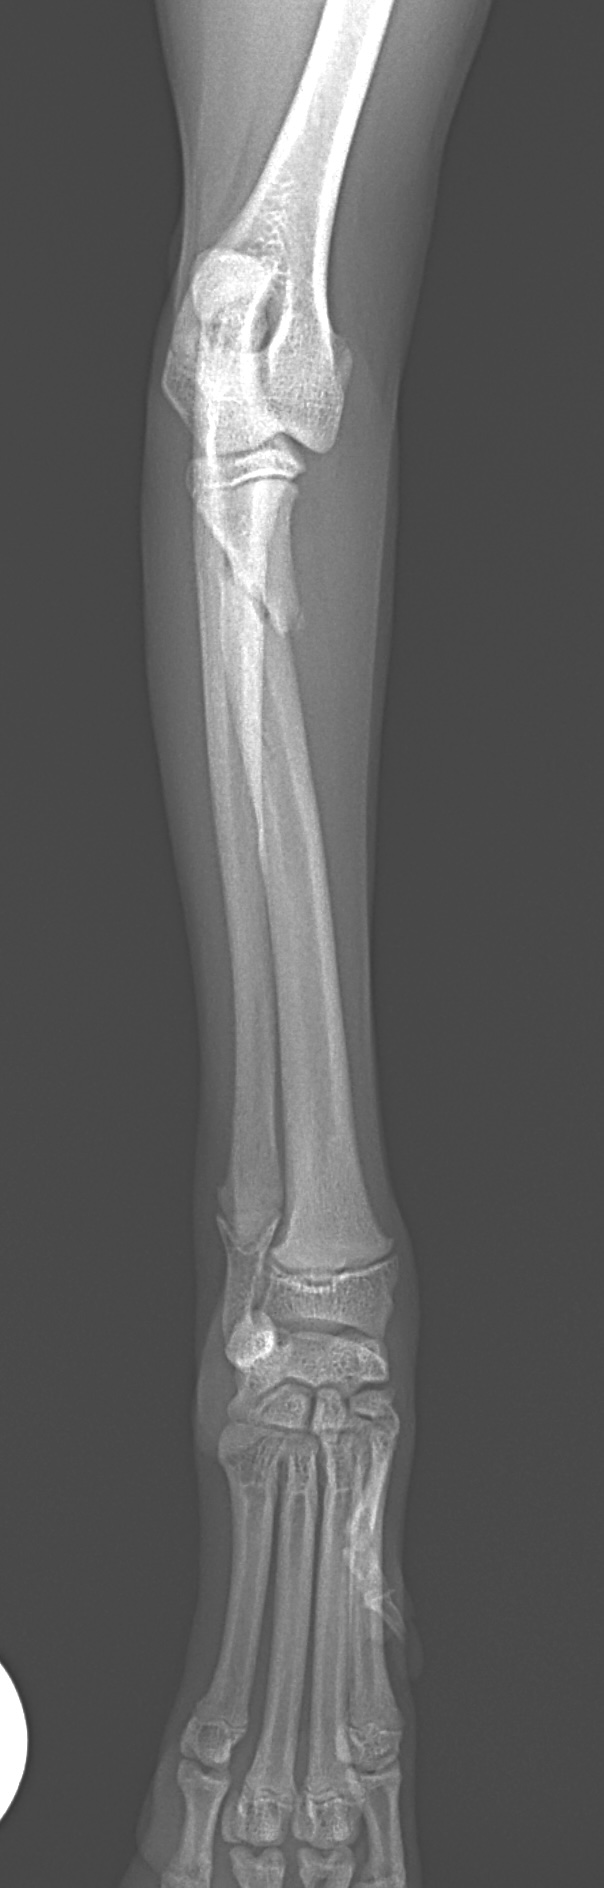

橈骨固定術 #240

Toy Poodleさんがソファーより転落後に橈骨近位を斜骨折したとの事。1.5 Locking Plateで固定術を実施しました。 しばらく安静が必要です。